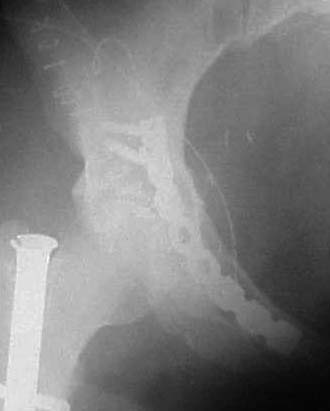

Look at your dome axial postoperative image...see the acetabular side fracture impaction injury adjacent to the dome medially?...also see the minimal residual fracture distraction? these two situations combined cause the femoral head to be incompletely centered beneath the dome (seen on the 3rd axial postop image)...see how the head is only slightly medially located relative to the dome???